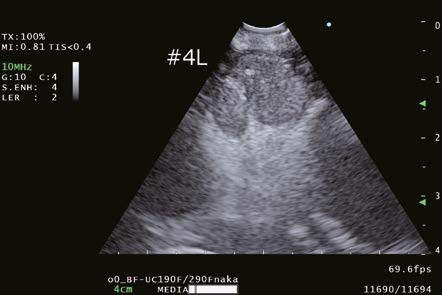

4L Lymph node puncture

During an EBUS-TBNA case, the position of the aspiration needle, especially the tip of the needle was well visualized and artifacts due to the needle itself were reduced. The enhanced image quality of the B-mode may contribute to making EBUS-TBNA procedures safer and more effective.